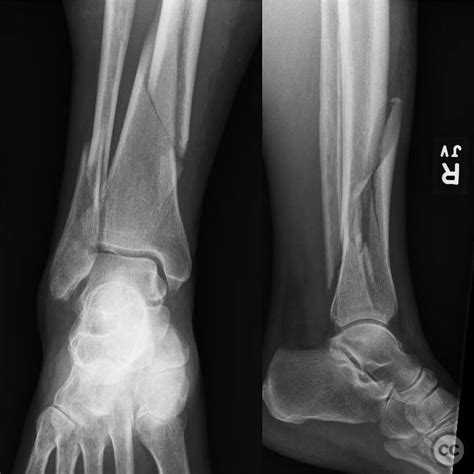

A non displaced fracture occurs when a bone breaks but the bone fragments remain in their original position. This type of fracture is often less severe than displaced fractures, where the bone fragments are misaligned. Non displaced fractures can occur in any bone in the body, but they are most commonly seen in the wrist, ankle, and spine. These fractures are typically the result of minor trauma, such as a fall or a direct blow to the bone.

Non displaced fractures are often classified based on the type of bone involved and the mechanism of injury. For example, a non displaced fracture in the wrist might occur due to a fall on an outstretched hand, while a non displaced fracture in the spine might result from a compression injury. Understanding the specific type of non displaced fracture is essential for determining the appropriate treatment and recovery plan.

• Imaging Studies: X-rays are the most common imaging tool used to diagnose non displaced fractures. They can provide a clear view of the bone and help determine the location and extent of the fracture. In some cases, additional imaging studies such as CT scans or MRI may be necessary to get a more detailed view of the injury.